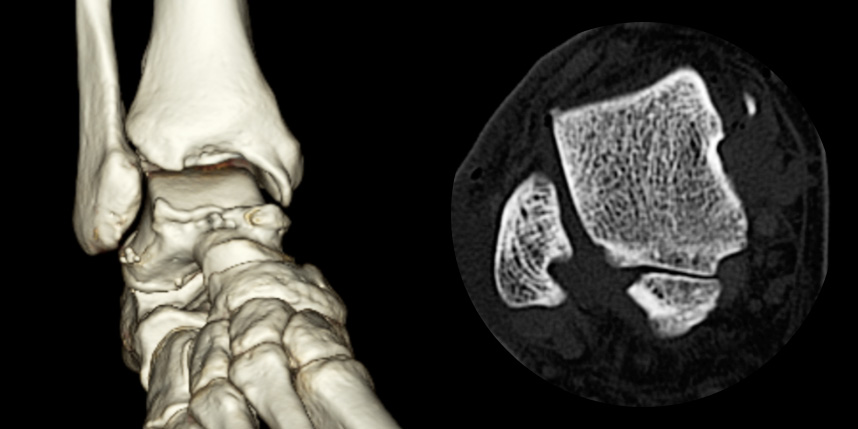

환자 자신의 건강한 연골을 채취하여 손상된 부위에 이식하는 방법으로, 발목 연골 손상에 주로 이용하며 정상 연골을 채취해야 하기 때문에 공여부(donor site)의 문제가 있을 수 있다는 점이 최대 단점입니다.

타병원 미세천공술 실패 후 통증으로 내원하신 사례

* 환자에게 받은 소중한 자료입니다.